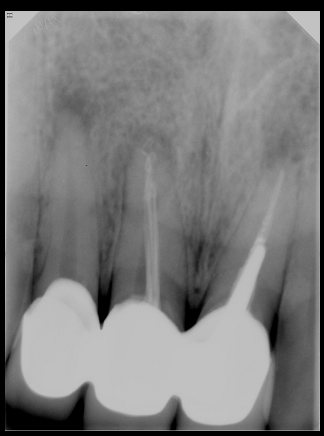

CR/DR 牙齿分割阶段记录

当前进展

- 完成了 CR/DR 牙齿相关分割训练

- 当前结果已经达到阶段预期,但仍有细节问题需要继续处理

相关测试

遇到的问题

- 训练过程中出现过 mask 下移问题

- 部分结果会出现 box 填充异常

- mask 边缘仍然有比较明显的锯齿感

参考

第三版算法分辨率效果比较

Updated: 2026-04-13(更新日期)

| 编号 | 原图 | 第一版 | 第二版 | 第三版 1216x1600 | 第三版 768x1024 | 第三版 1120x1120 |